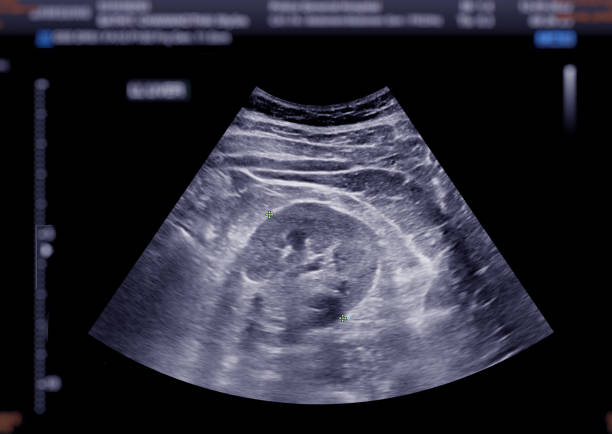

3. Obstetric Ultrasound – Essential for monitoring pregnancy, tracking fetal development, and detecting any abnormalities at various stages.